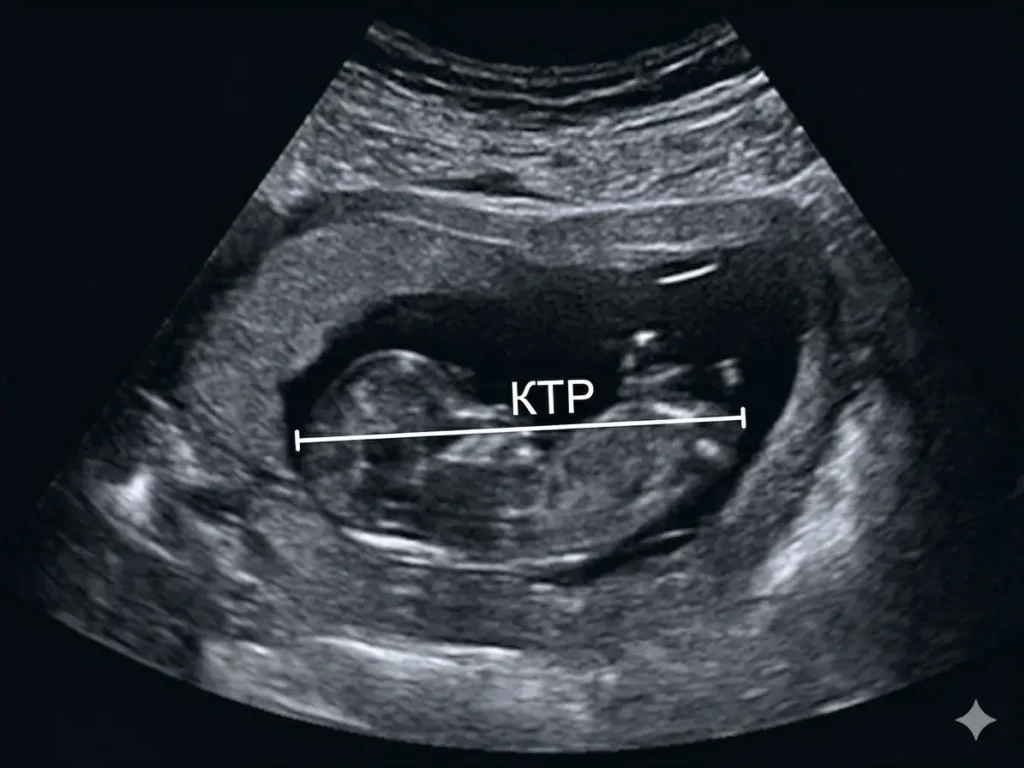

КТР (копчиково-теменной размер) — это фактическая длина эмбриона от копчика до макушки головы, измеряемая во время ультразвукового сканирования. Простыми словами, это максимальная дистанция от задней части туловища до самой высокой точки головы. Важно понимать, что на ранних этапах ножки плода еще не учитываются в общую длину, поскольку они согнуты или находятся в стадии формирования, поэтому именно КТР становится наиболее репрезентативным показателем.

Во время процедуры врач ищет сагиттальную плоскость сканирования — это такой ракурс, при котором плод виден в профиль в максимально разогнутом состоянии. Если малыш слишком согнут или, наоборот, слишком активен, врач может попросить пациентку сменить положение или подождать несколько минут, пока эмбрион сменит позу. Это необходимо для того, чтобы измерительная линия прошла ровно от копчика до темени, не создавая ложных результатов.

После получения четкого стоп-кадра специалист ставит электронные маркеры на крайние точки тела плода. Современные аппараты автоматически сопоставляют полученный результат в миллиметрах с внутренней базой данных и выдают срок беременности с точностью до дня. Важно, чтобы обследование проводилось на оборудовании экспертного класса, ведь даже ошибка в 1-2 мм на раннем сроке может привести к неправильной трактовке развития ребенка.